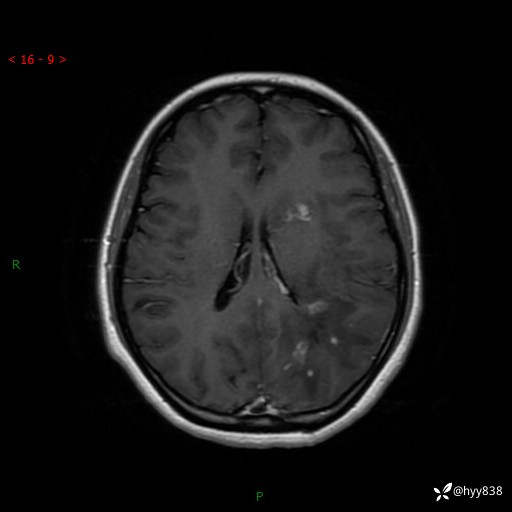

颅脑MRI平扫+增强